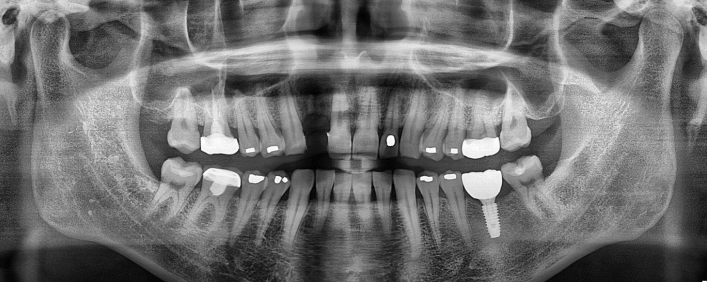

임플란트 치료사례

서울스마트치과는 결과로 증명합니다.

위 치료 사례는 서울스마트치과에서 직접 치료를 받고, 환자 본인의 동의를 얻어 게재된 사진으로 무단 인용, 도용, 재배포 시 민/형사상 책임을 질 수 있습니다.